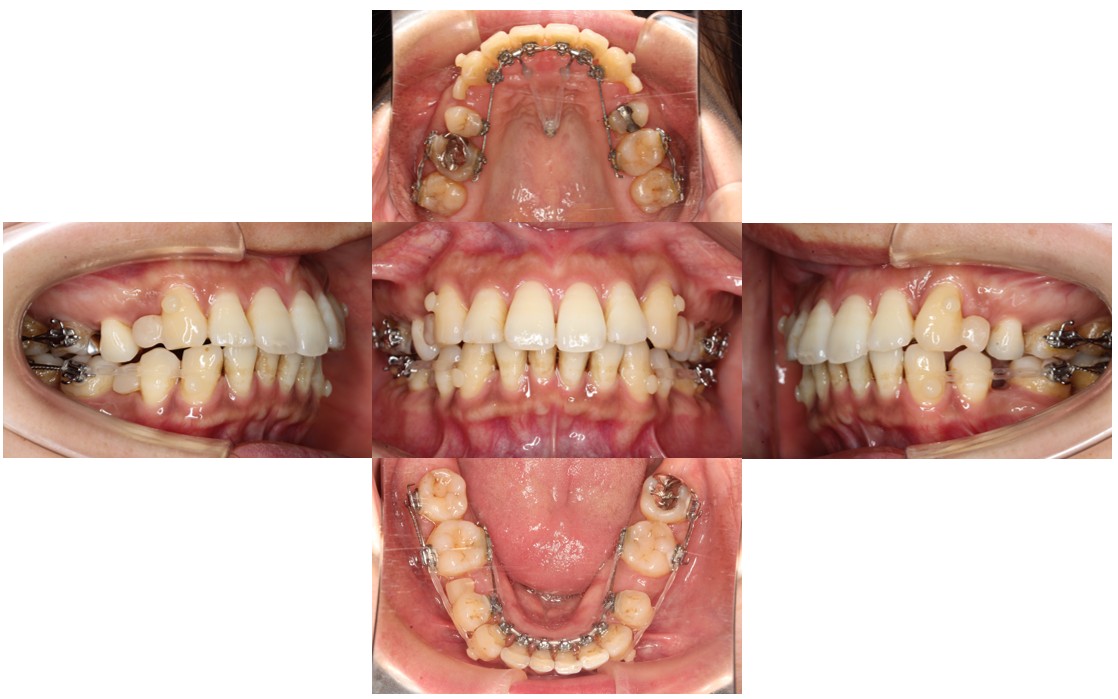

9ヵ月経過の口腔内の状態です。

全体の凸凹が改善しました。

一部表側にも装置をつけ、効率良く奥歯も動かしてかみ合わせを整えています。